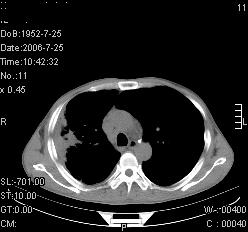

患者,男,54岁,咳嗦,咳痰20天。抗炎治疗2周。现esr76mm/h,目前患者症状明显好转,但发现两次ct片未见明显变化。两次分别做与7.25、7.31。第一次诊断右肺上叶炎症累计胸膜。大家看,从影像上内排除结核吗?

结核的可能性非常大,右上肺病变应该考虑干酪性肺炎。理由:

1.纵隔内多发淋巴结肿大。

2.esr76mm/h。

3.虽经抗炎治疗肺窗病灶有所吸收、减小,但纵隔窗病灶形态、密度、范围无明显变化。如果是单纯的大叶性肺炎,“抗炎治疗2周,目前患者症状明显好转”病灶应该基本消散了,至少也处于吸收消散期,密度变淡、范围变小。同时本病例所示其内的密度不均匀,见多发大小不一空洞样影也不符合大叶性肺炎吸收消散期表现。